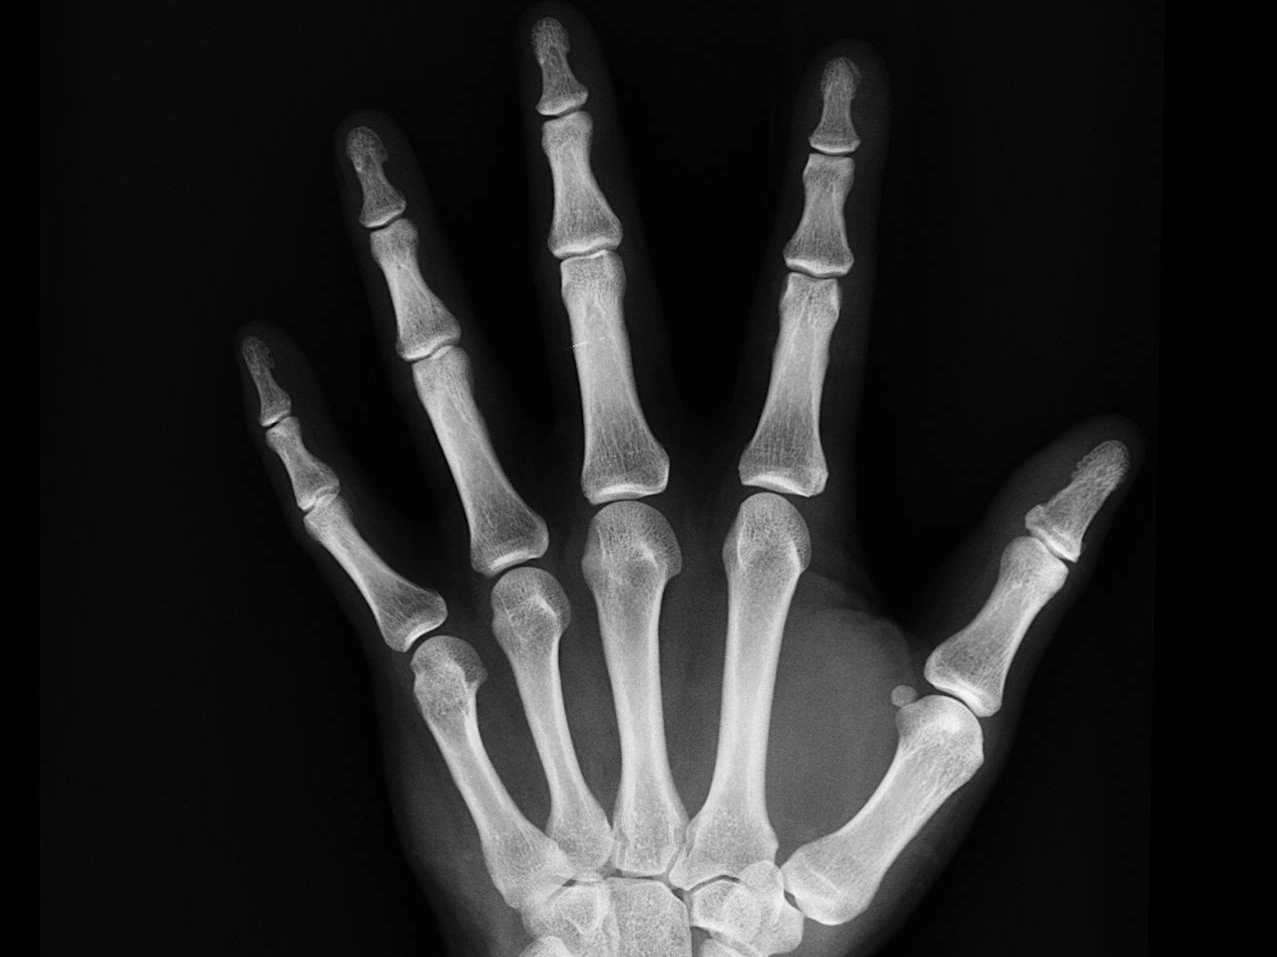

Radang Sendi Jari Tangan: Penyebab, Gejala, dan Pengobatannya

Radang sendi jari tangan merupakan salah satu keluhan yang cukup sering ditemui, terutama bagi Anda yang aktif menggunakan tangan untuk berbagai aktivitas sehari-hari. Mulai dari mengetik, memasak, hingga bermain alat musik, semua memerlukan kelincahan dan kekuatan jari yang sehat. Tapi, ketika radang sendi menyerang, aktivitas tersebut bisa menjadi terasa menyiksa. Artikel ini akan membantu Anda […]